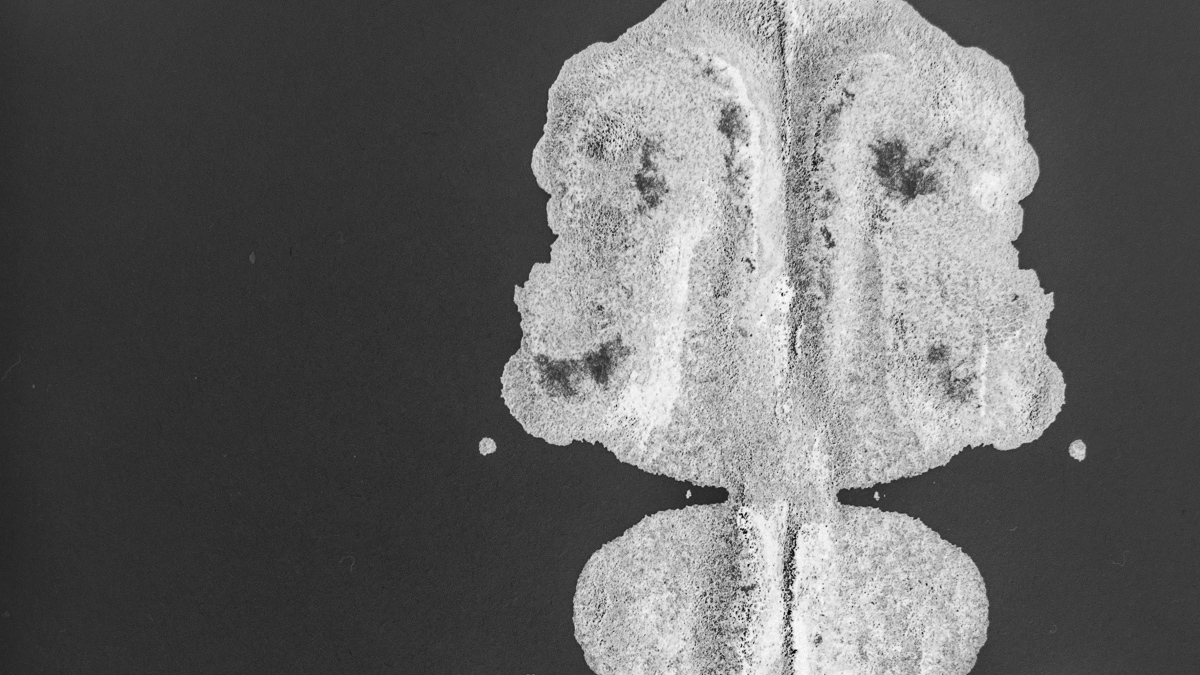

Oppiminen ja rentoutuminen auttavat aivoja

Kuten monissa asioissa elämässä, myös stressissä on hyviä ja huonoja puolia. Tavallisesti keskitymme stressin negatiiviseen puoleen ja tämä itsessään myös lisää stressin haitallisia vaikutuksia. Helsingin yliopiston aivotutkija Katri Saarikivi kertoo YLE Akuutin artikkelissa stressistä.